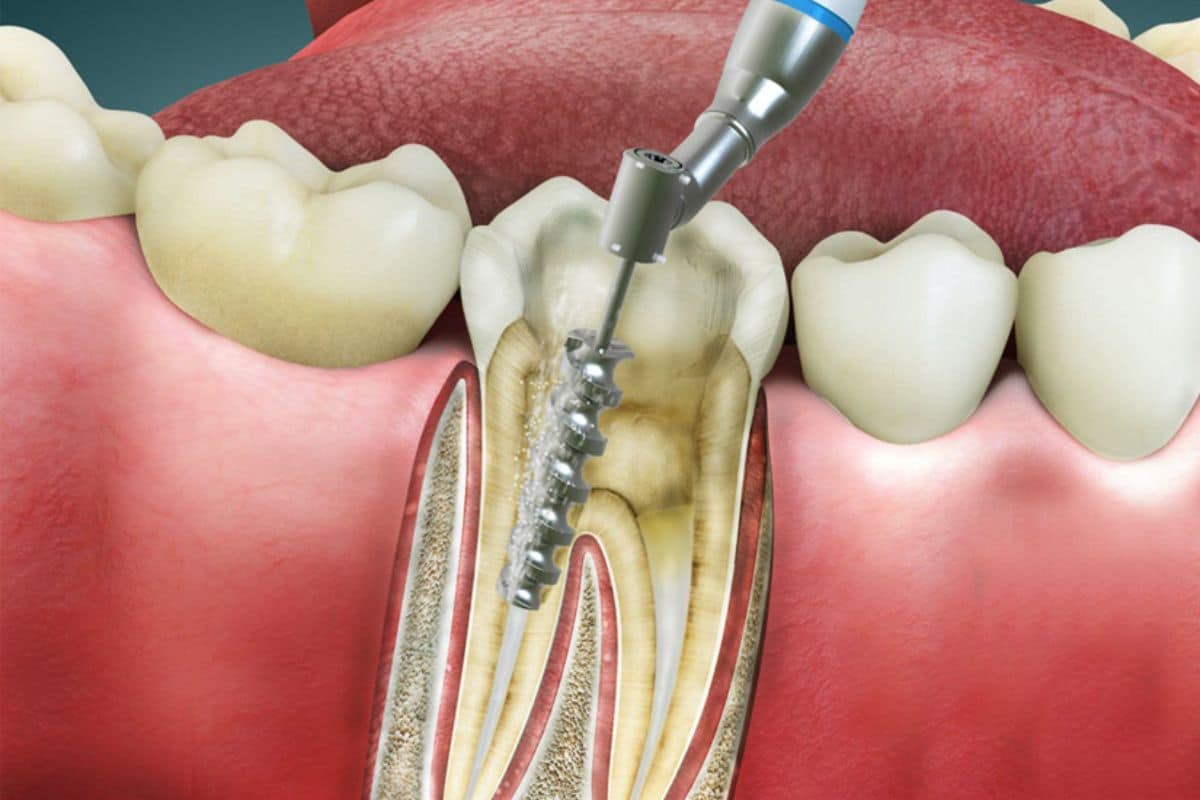

Root Canal Treatment

Root canal treatment in Türkiye

Don’t let tooth pain hold you back. Our advanced root canal treatments will relieve your discomfort and preserve your natural smile.

At Dream  Clinic, our expert dentists use state-of-the-art techniques to perform root canal treatments with precision and comfort, restoring your dental health and preserving your smile.